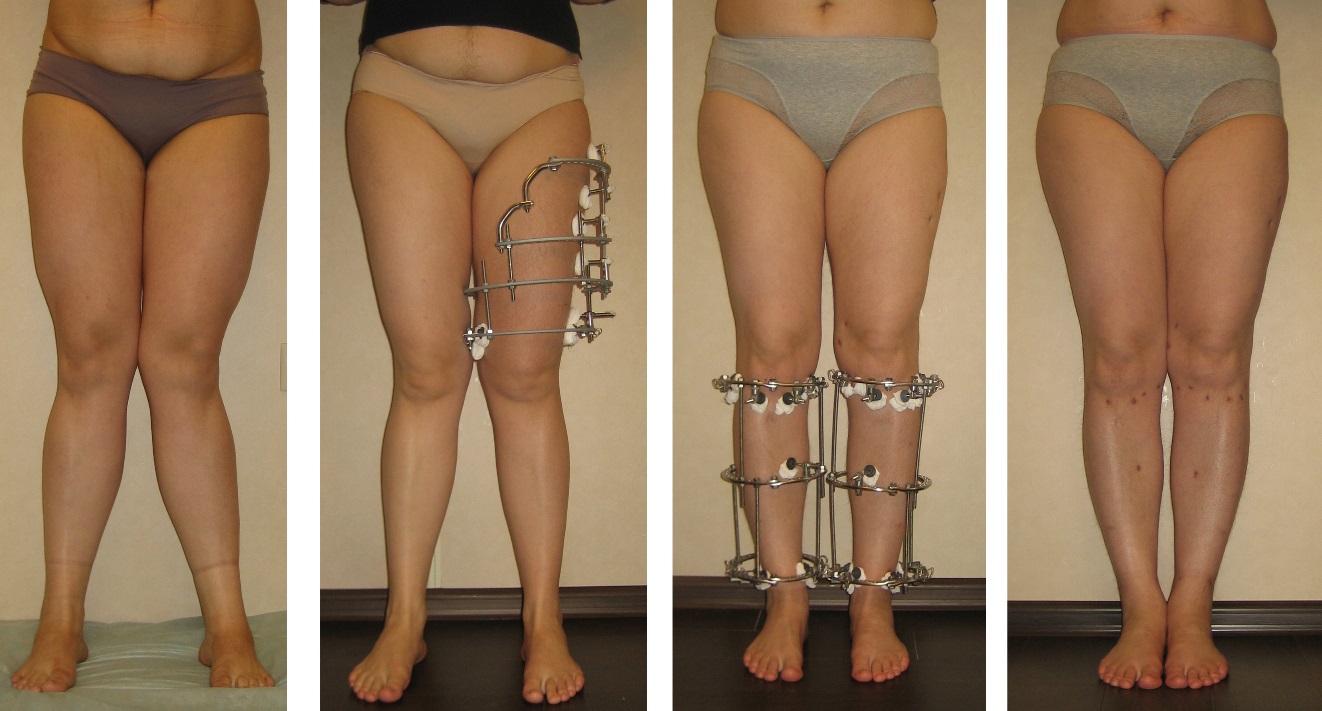

Аппарат Илизарова: принцип работы и применение